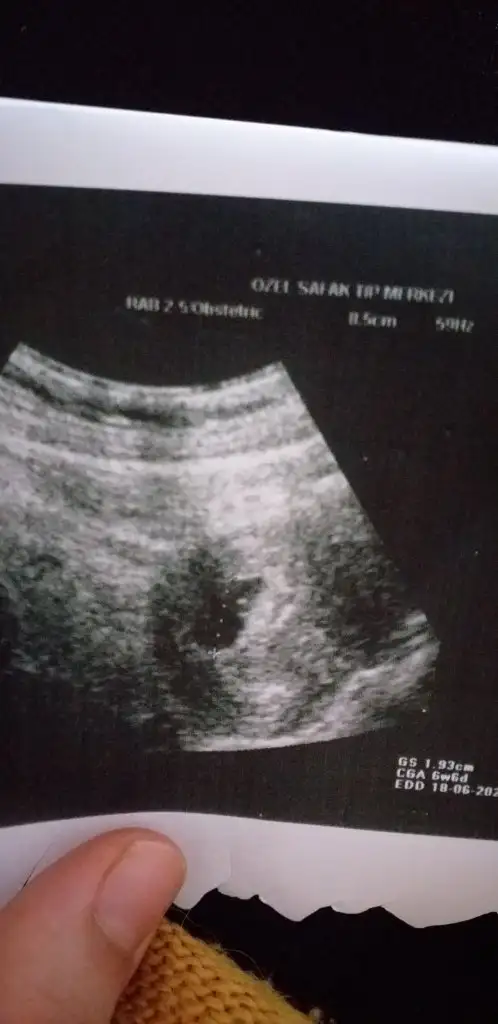

6+6 karından bakıldıysa kız vajinal bakıldıysa erkek digeri kaç hafta yazmıyor

Karindan bakildi o da 8 haftalik6+6 karından bakıldıysa kız vajinal bakıldıysa erkek digeri kaç hafta yazmıyor